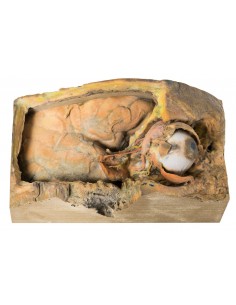

3D Anatomy 1.0 - Extremidades inferiores

Venas superficiales del miembro inferior Erler Zimmer 3D anatomy Series MP1815